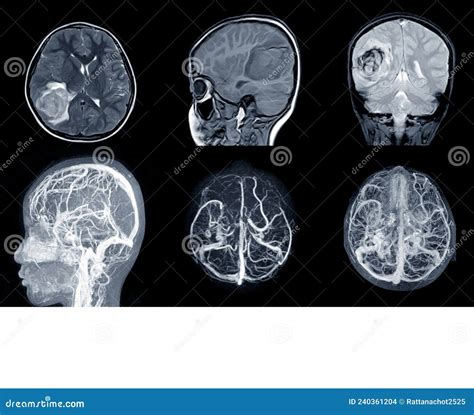

Magnetic Resonance Angiography (MRA) is a specialized application of MRI technology specifically designed to examine blood vessels. While a standard MRI looks at anatomy, an MRA is focused on hemodynamics—the way blood flows through your circulatory system. By manipulating the MRI machine's settings, doctors can highlight blood vessels and create a map of the vascular network.

MRA is primarily used to detect issues such as aneurysms, arterial blockages, narrowing of the vessels (stenosis), or vascular malformations. It is particularly valuable for identifying risks of stroke or heart disease. Because MRA provides a 3D visualization of blood flow, it acts as a critical tool for surgeons and radiologists planning interventional procedures.

After the scan is completed, the raw data is reconstructed into high-resolution images by the radiology software. A radiologist will then analyze these images, looking for abnormalities, comparing them to previous scans if available, and generating a detailed report for your primary physician. This process usually takes a few days, at which point your doctor will review the findings with you to discuss the next steps in your treatment plan.